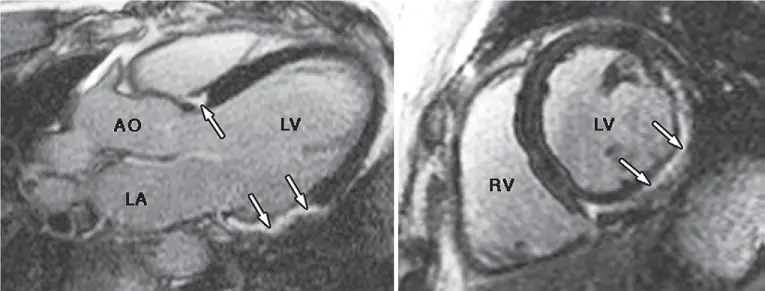

47歲男性,曾頭暈昏倒多次,心電圖檢查顯示多發性心室期外收縮。磁振造影發現左心室較大,下壁及下外側壁收縮功能較差,顯影劑注射後,磁振造影出現顯影劑延遲增強(late gadolinium enhancement, LGE),如附圖所示。下列敘述何者錯誤?

影像分析:

左圖(4腔向)及右圖(短軸向)均見左心室下壁與下外側壁 (inferior & inferolateral walls) 心肌中外層明顯增強區域 (白色箭頭)。此增強不符合單一冠狀動